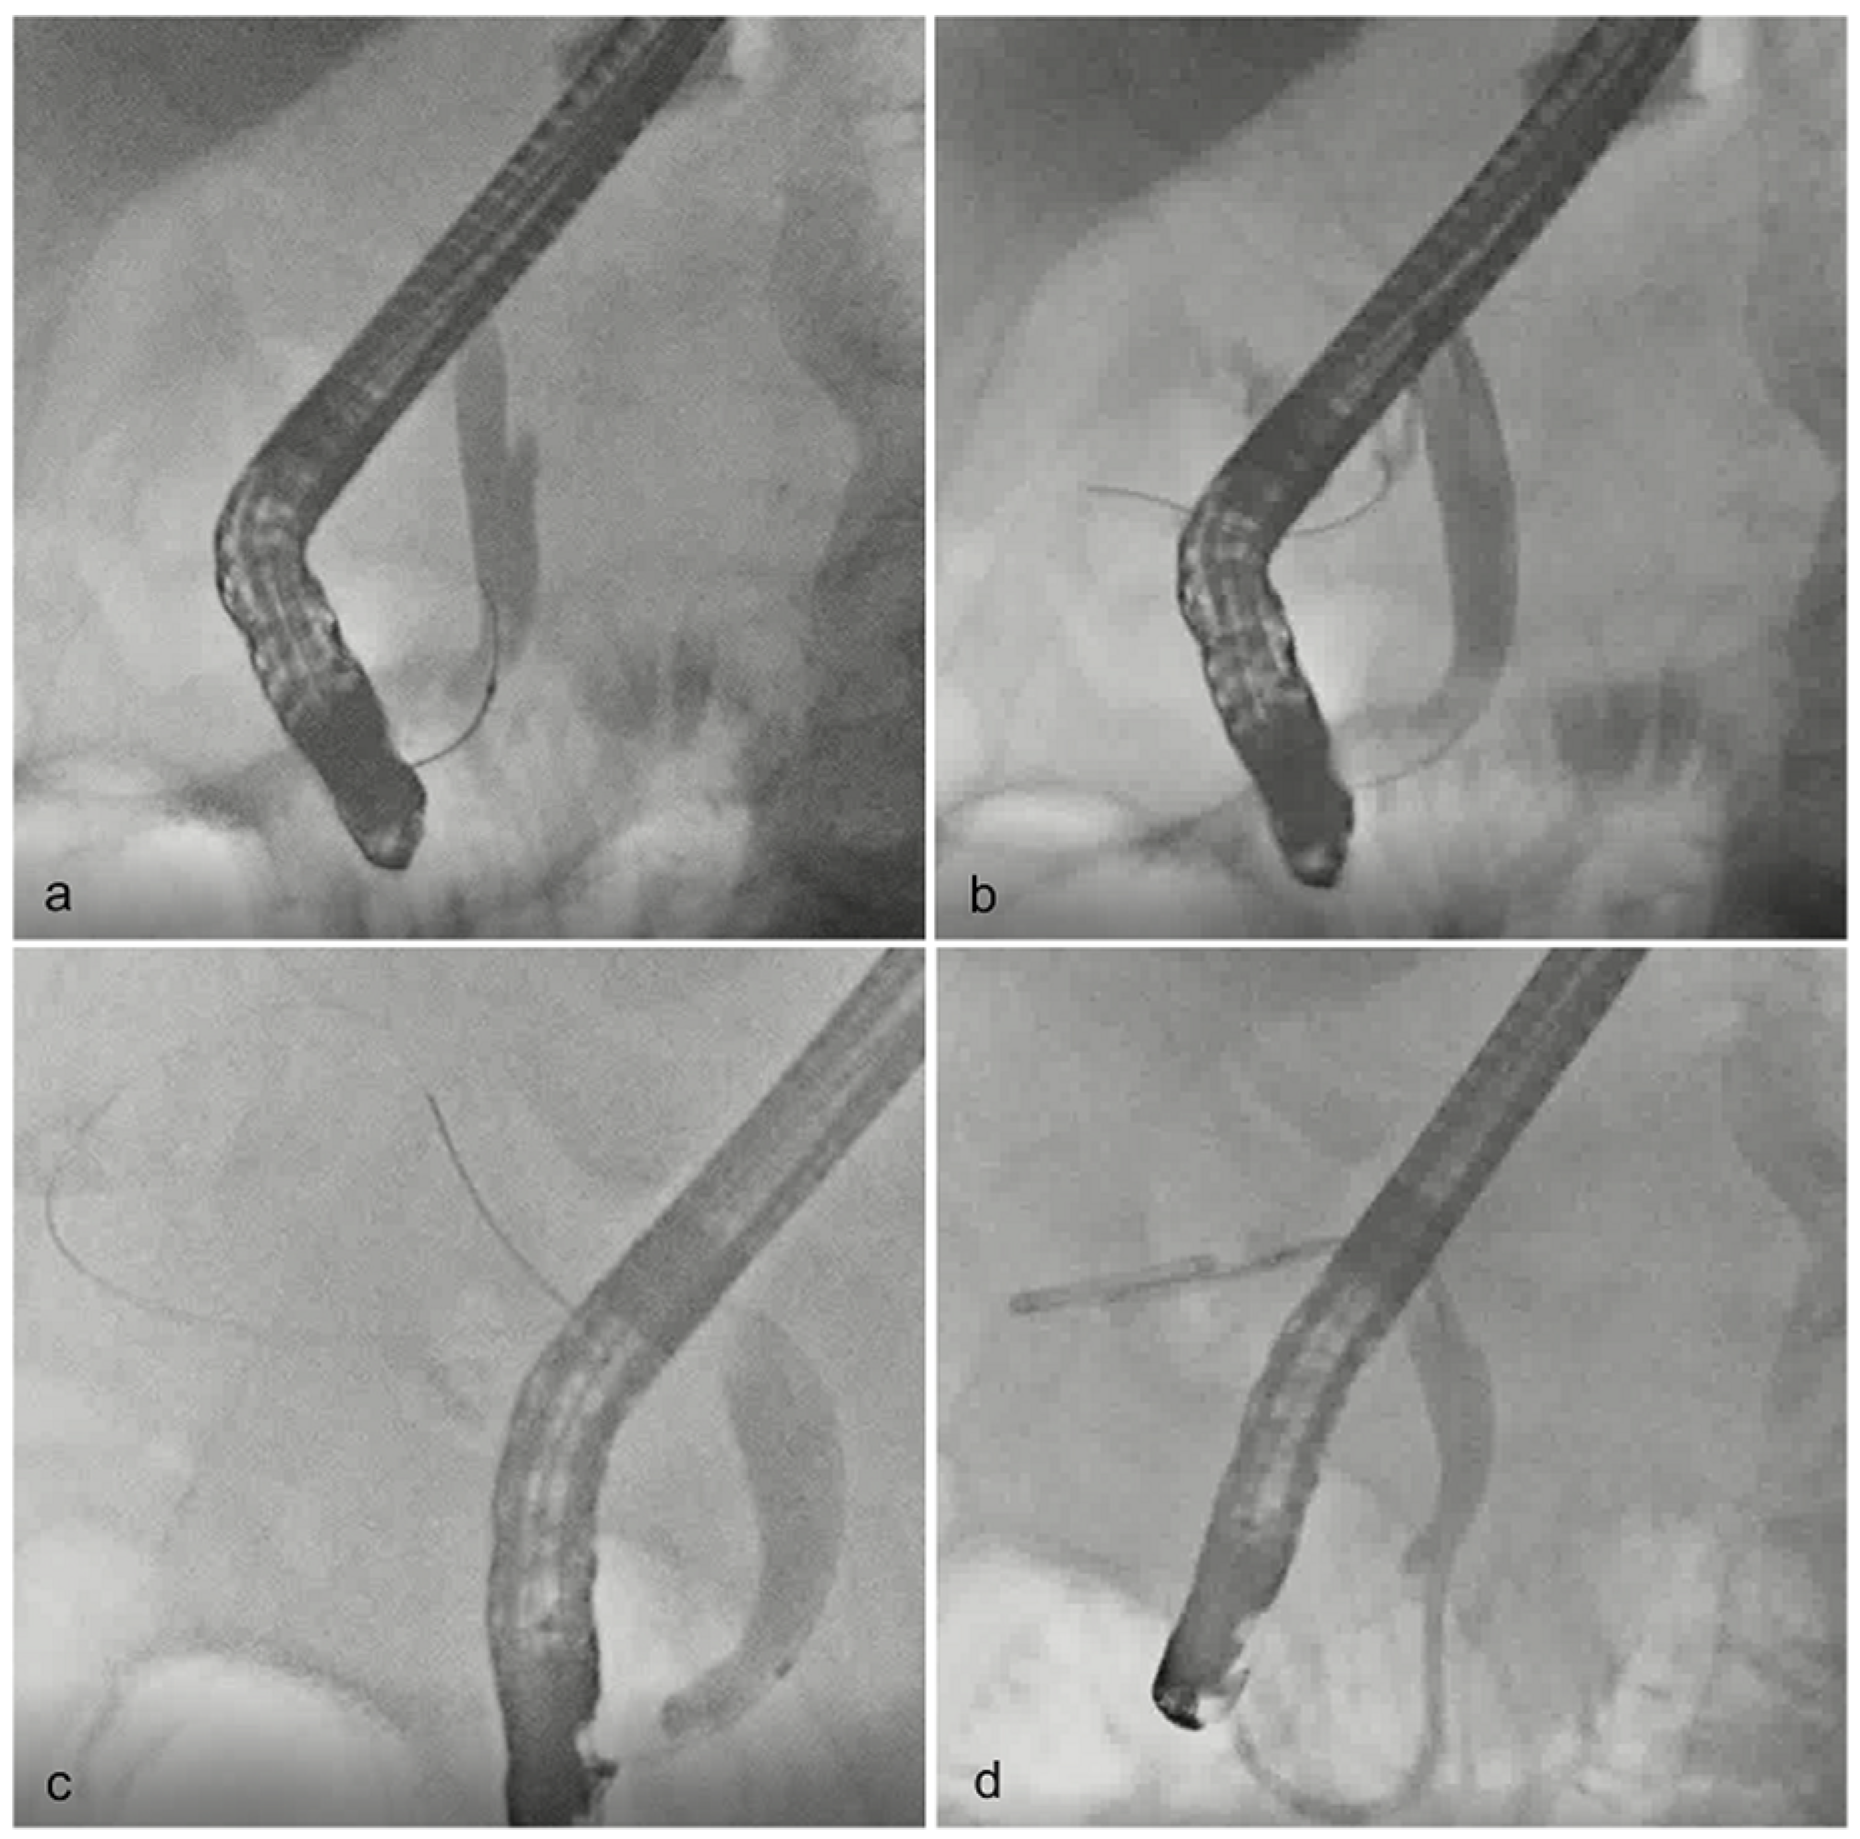

Endoscopic gallbladder stenting. The cystic duct was sought with a

Endoscopic gallbladder stenting. The cystic duct was sought with a Endoscopic Of Gallbladder Endoscopic gallbladder drainage can be considered in patients without evidence of gallbladder perforation or biliary peritonitis. Endoscopic ultrasound (eus) has a high spatial resolution that can improve the diagnosis of gb polypoid lesions, gb wall. Whether the approach to the management of gallbladder disease is surgical, endoscopic (as in the fairly recent introduction of natural orifice. Diseases of the gallbladder. Endoscopic Of Gallbladder.